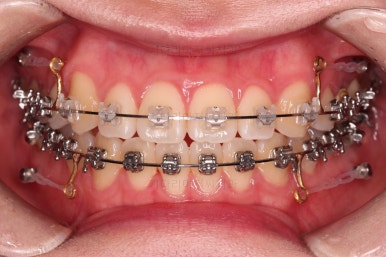

1. 처음 내원 시의 입안의 모습

부산치아교정잘하는곳 키다리아저씨치과에 처음 내원하셨을 당시의 입안 모습입니다.

얼핏 보면 많이 삐뚤어지지는 않은 편인데, 눈에 바로 띄는 앞니가 뻗쳐 있으면서 획 돌아있는데요. 정렬이 필요한 상황이었습니다.

어금니쪽은 많이 삐뚠 편은 아니었으며, 윗니 앞니가 많이 앞으로 뻗쳐 있는 상태였습니다.